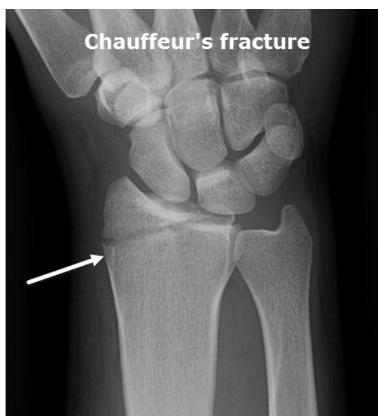

What fracture is this?

Hutchinson (Chauffeur)

What is a Hutchinson (Chauffer) fracture?

Special

Fx of radial styloid process (blow to lateral side of distal forearm)